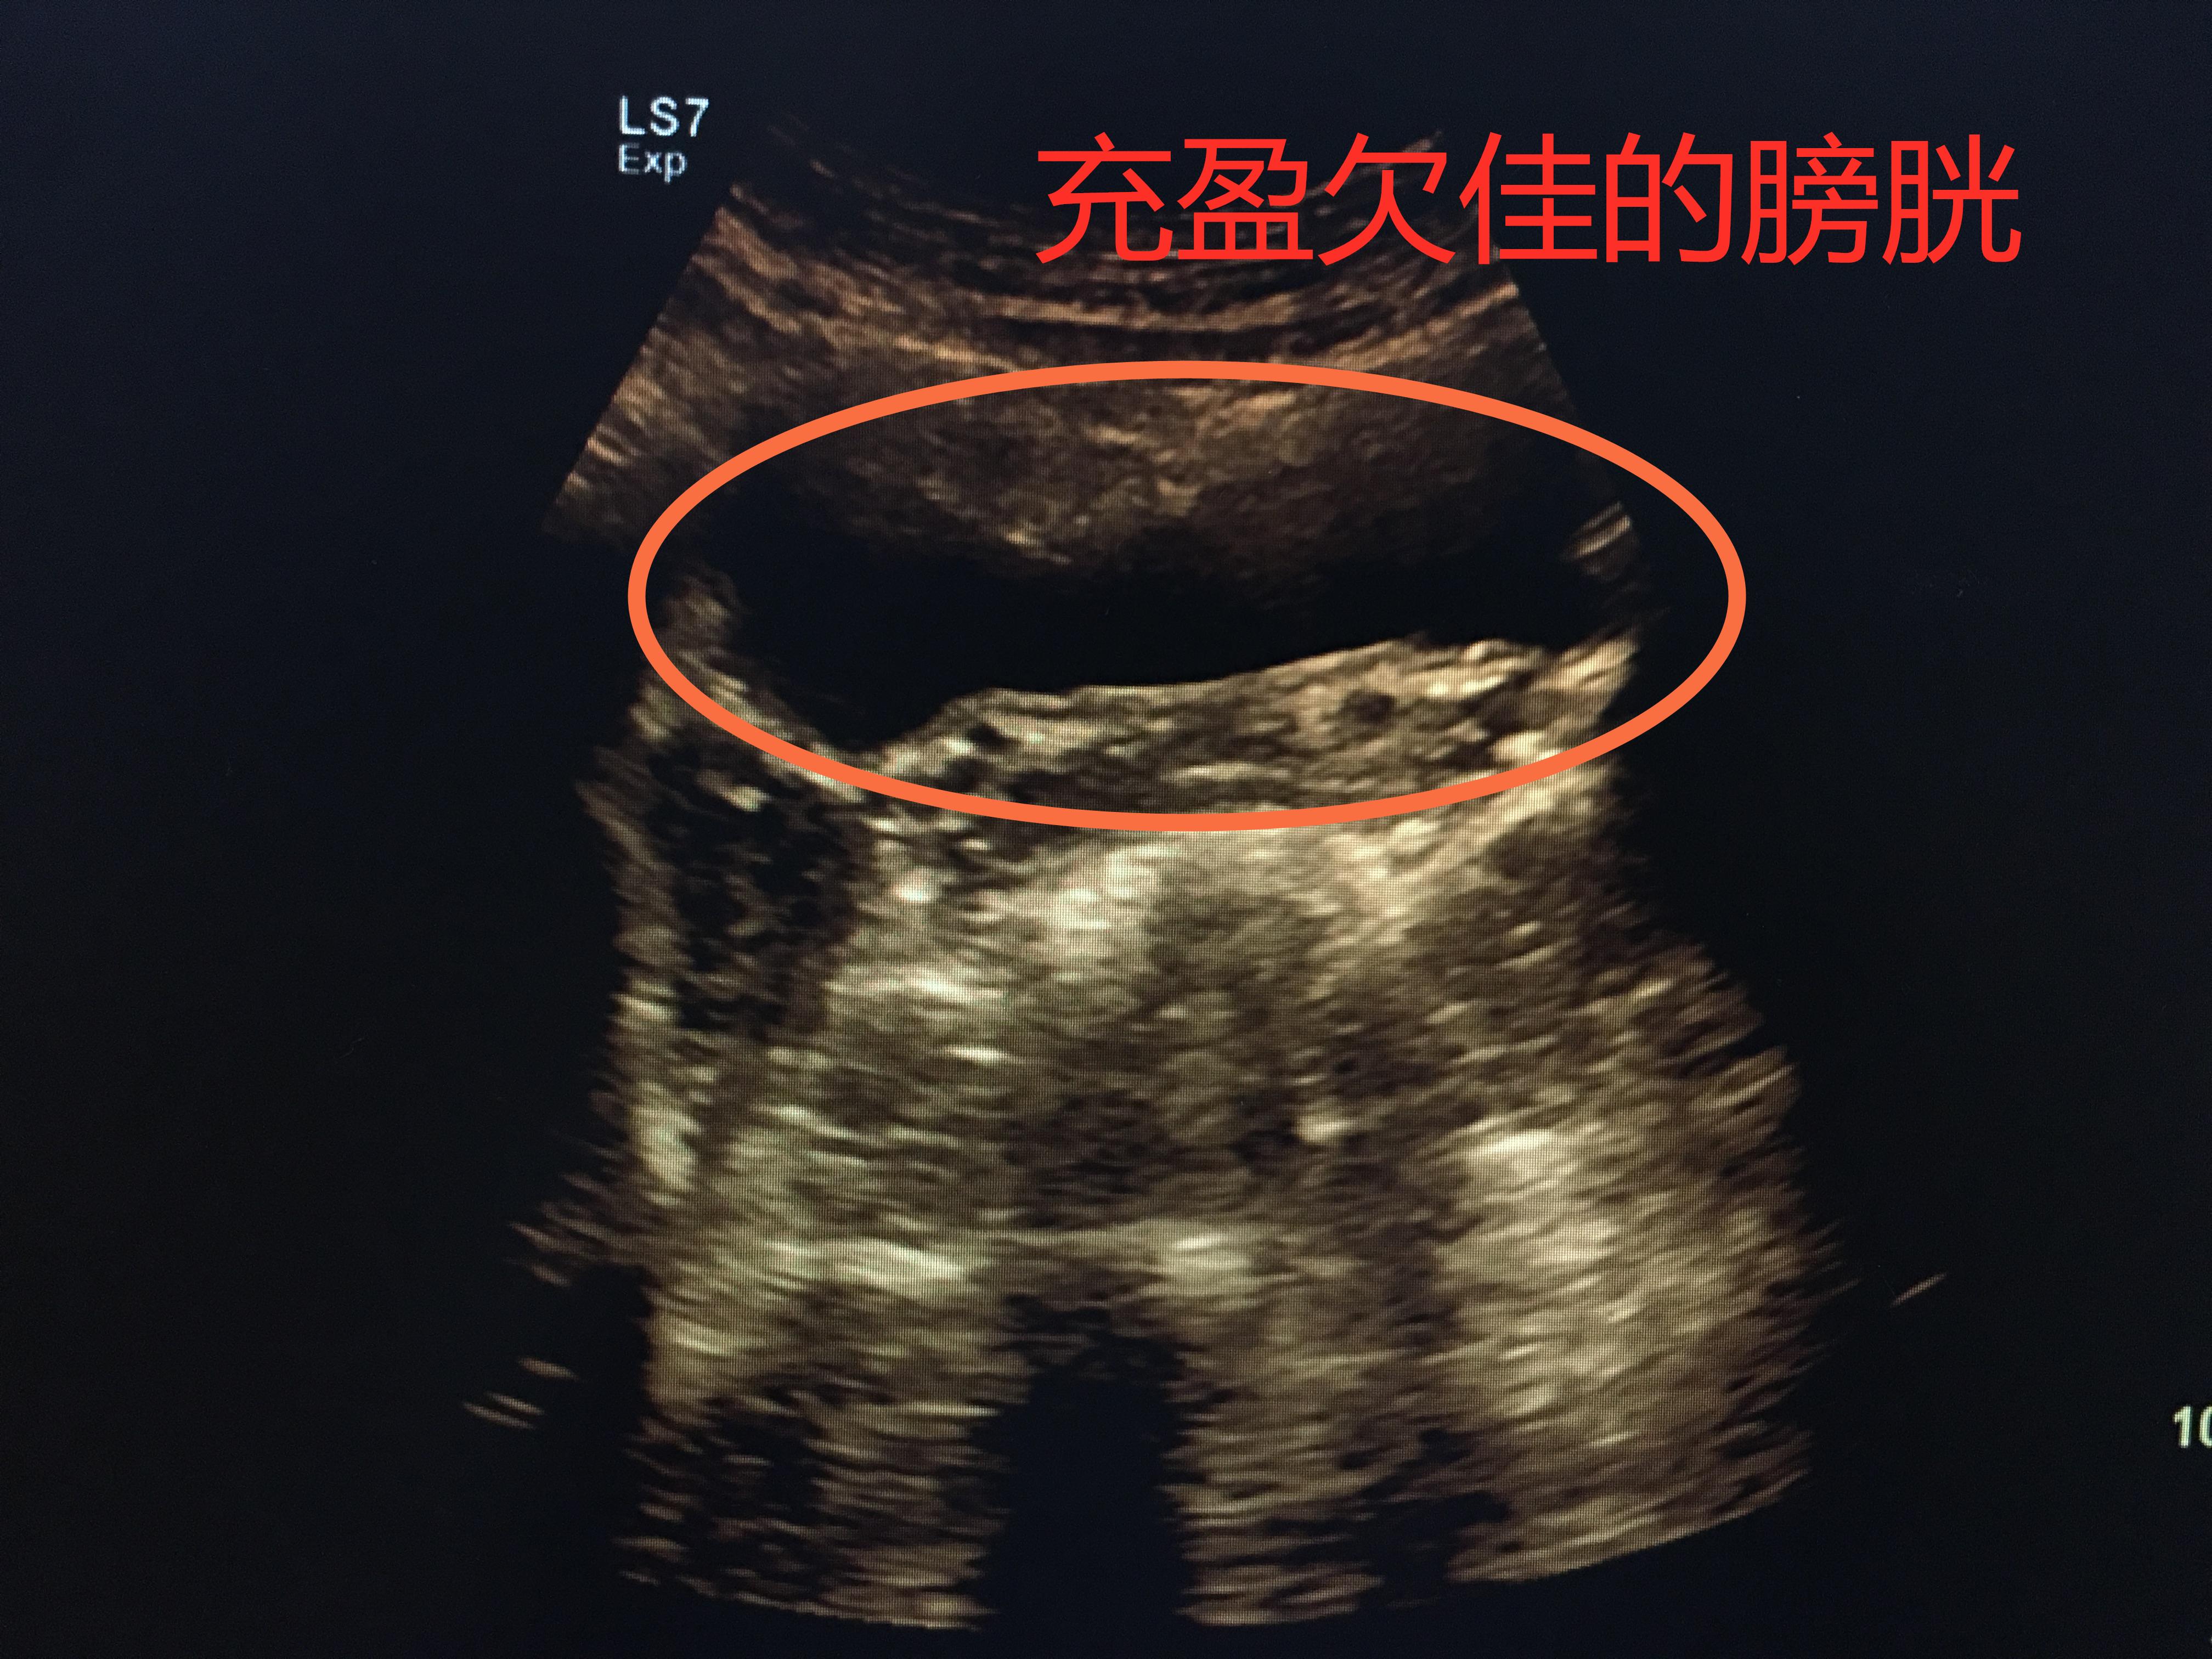

憋尿欠佳,膀胱欠充盈

膀胱就像一个皮球,当你往里面打足气时,皮球便充分撑开;而当打的气不够时,皮球就瘪着。所以,当你憋尿充足时,膀胱充盈起来,把每个角落都撑开,检查时便一览无遗;当憋尿不够,充盈欠佳时,局部可能皱褶起来,隐藏病灶。所以,下次医生让你憋尿的时候,就努力的憋吧。